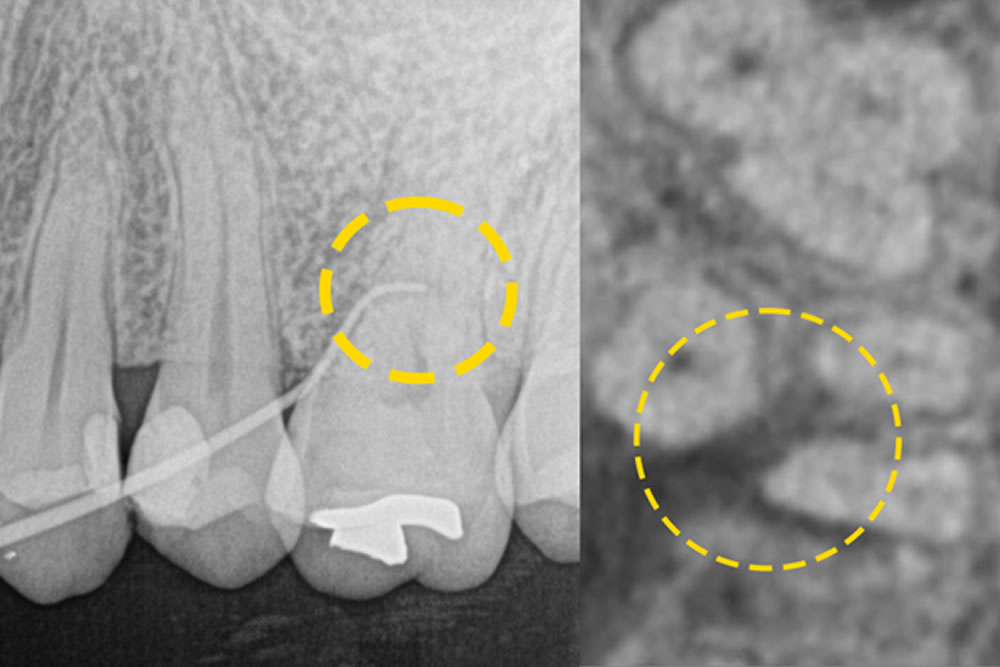

こちらの患者さまは、左上の第一大臼歯の近心部に「垂直性骨欠損」が認められ、歯周病の進行により歯を支える骨が深く失われていました。また、同じ歯の根の分かれ目(分岐部)にも炎症が広がっており、「根分岐部病変」という状態でした。これは、歯の根が分かれている部分まで歯周病が進行し、プローブが分岐部の中ほどまで届くような中等度の病変を意味します。

このような症例では、通常のクリーニングや歯周ポケットの治療だけでは改善が難しいため、当院では最小侵襲手術(MIST)を行いました。マイクロスコープ(顕微鏡)を使用して分岐部の状態をしっかり確認し、Er:YAGレーザーを用いて感染した組織を丁寧に除去。さらに、骨の再生を促す処置(再生療法)も併せて行いました。